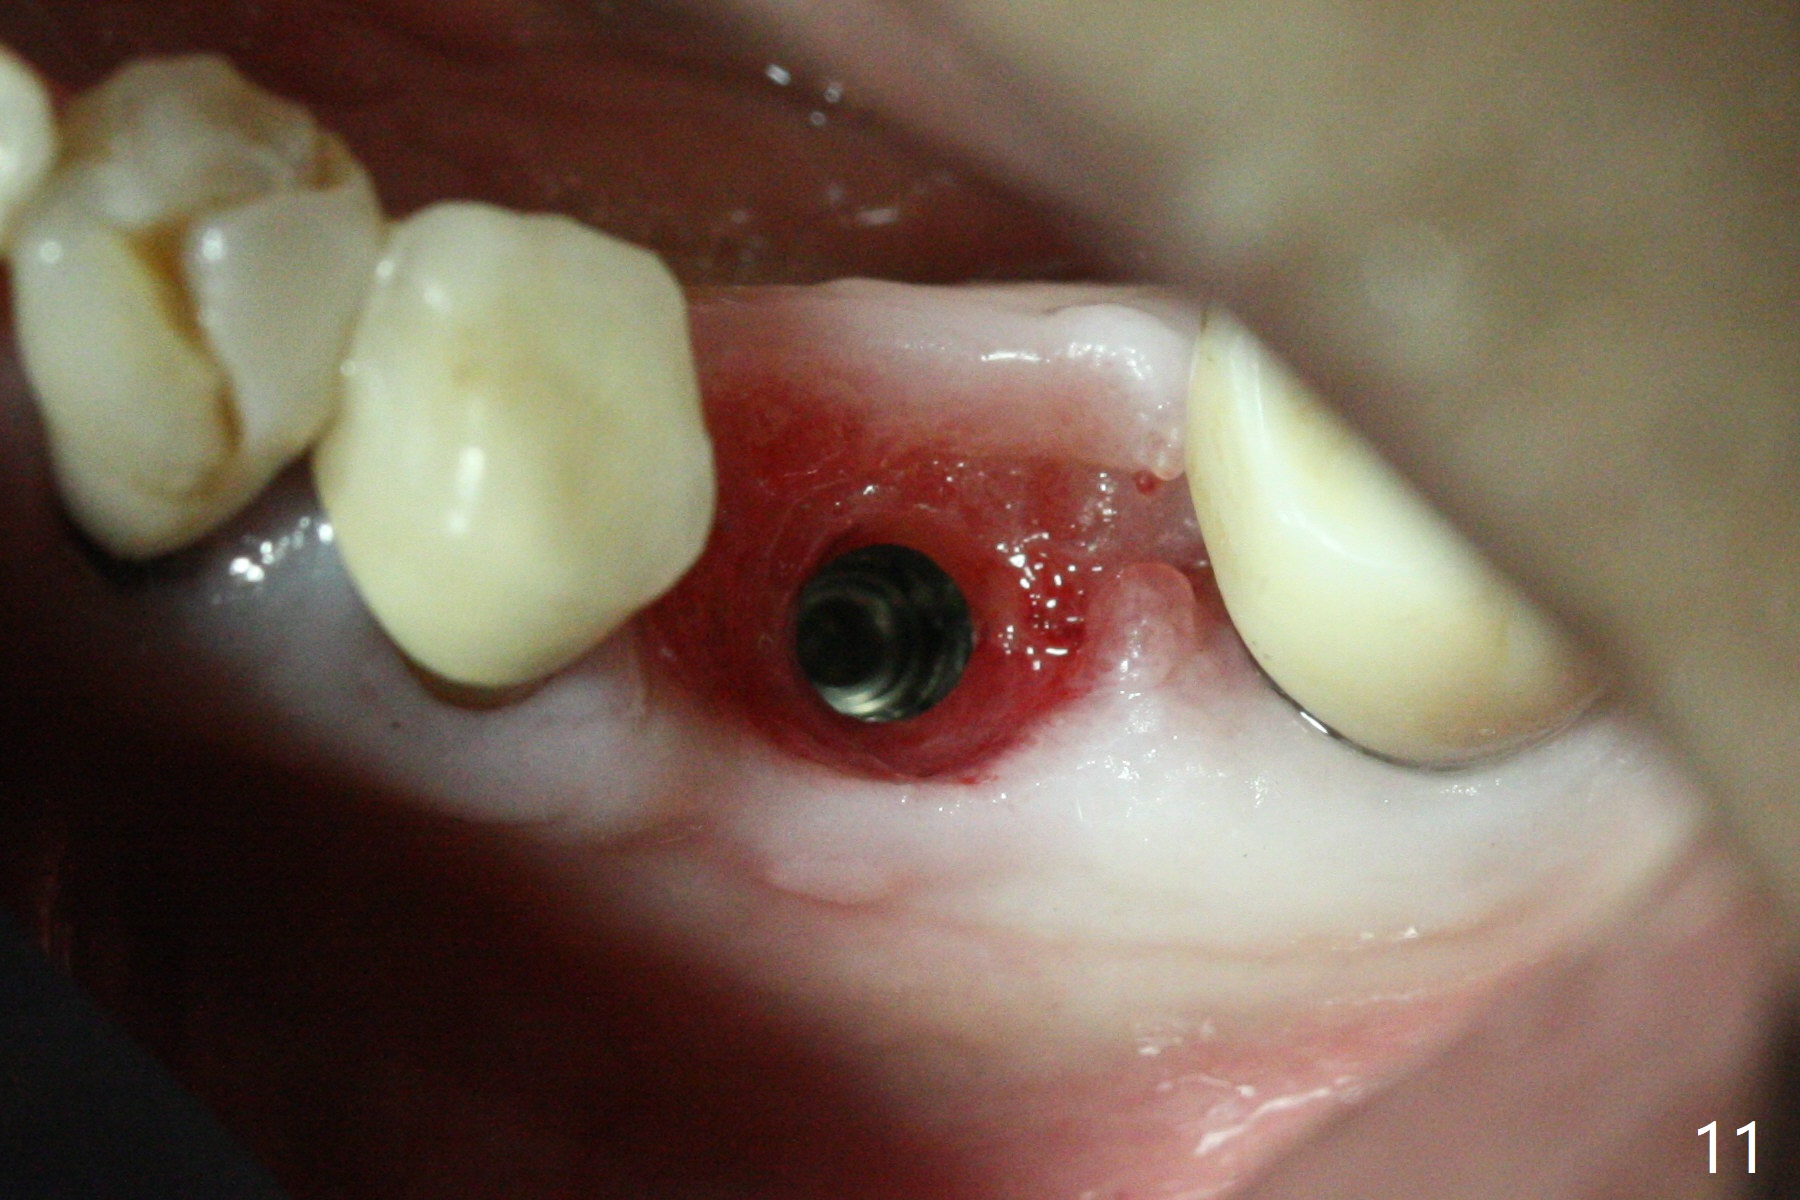

Extraction of the residual roots at #19 (Fig.1) is difficult, partially due to the hard one. The latter contributes to primary stability of 5x10 mm IS implant placed in the septum (Fig.2 (*),3). After change of cementation abutment (5.2x4.5(2) mm (short for provisional)) to hexed temporary abutment (5.2x8(2) mm), Collagen plug and Vera Graft are placed in the remaining mesial and distal socket (Fig.4 *). The last PA is taken when the temporary abutment (Fig.6 (<: hexed portion)) and provisional (P) are removed for modification. Before the abutment/provisional complex returns, a 2nd round of graft is placed (Fig.5 *). After the complex is seated, a 3rd round of graft is placed buccally (Fig.7). The temporary abutment is retightened 2 months postop (Fig.8). The implant appears to be osteointegrated 3.5 months postop (Fig.9). The gingiva looks healthy with (Fig.10) and without the provisional (Fig.11,12). It appears that there is no or minimal buccal plate loss. After insertion of a 5.7 x3 mm 15 degree (B-type) angled abutment (Fig.13) and height adjustment, impression is taken. The provisional is reseated after impression. The mesial bony defect seems to have been repaired nearly 8 months postop, 3 months post cementation (Fig.14 *). The bone density increases mesially 11 months post cementation (Fig.15).